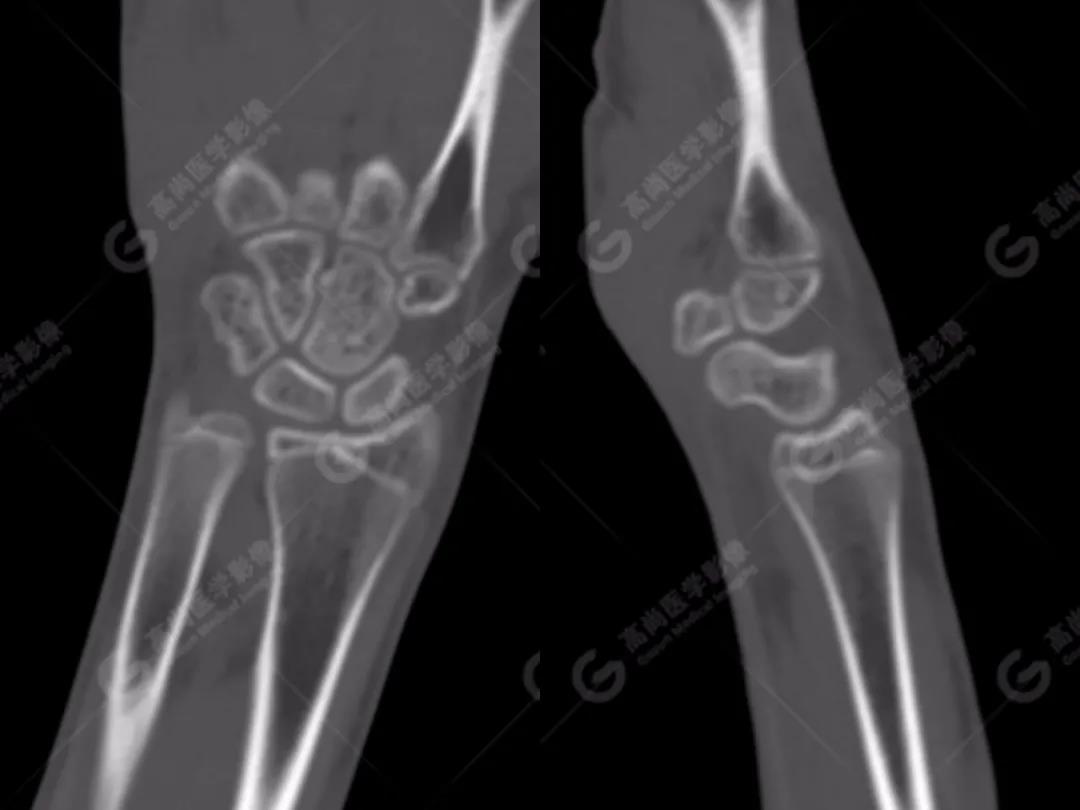

2、常規(guī)CT圖像

常規(guī)CT平掃灰階圖像上雙腕關(guān)節(jié)仍然未見明顯骨折征象。

3、雙能CT骨髓成像(雙能虛擬去鈣圖像)

高尚醫(yī)學(xué)影像診斷中心的Flash雙源CT可以利用雙能量骨髓成像來顯示骨骼內(nèi)的骨髓水腫,而外傷性的骨髓水腫往往提示骨挫傷或小梁微骨折。重建一下雙能虛擬去鈣骨髓圖像,進一步排除骨挫傷、微骨折。

雙能CT骨髓成像圖上發(fā)現(xiàn)了左側(cè)橈骨遠端和右側(cè)舟狀骨骨髓水腫(箭頭所示),進一步查體這兩處骨髓水腫剛好與患者的局部壓痛點相一致。